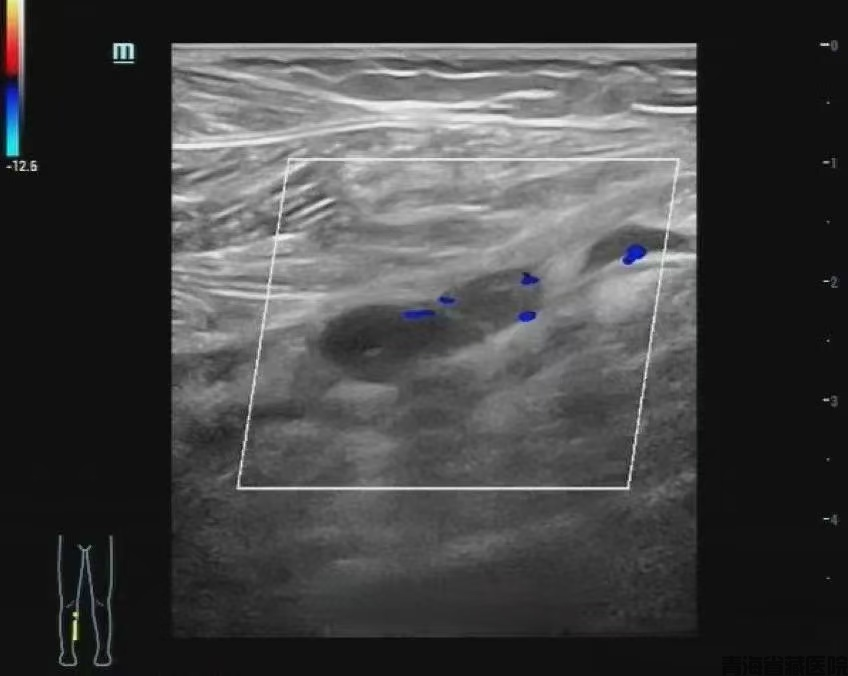

2)超声检查(准确率98%)表现:血管鼓胀变形呈"腊肠样"血流信号突然"消失"探头按压血管无法完全压扁

图片4.png

彩色多普勒超声检查

管腔内未见彩色血流信号,进一步提示静脉管腔内血栓形成